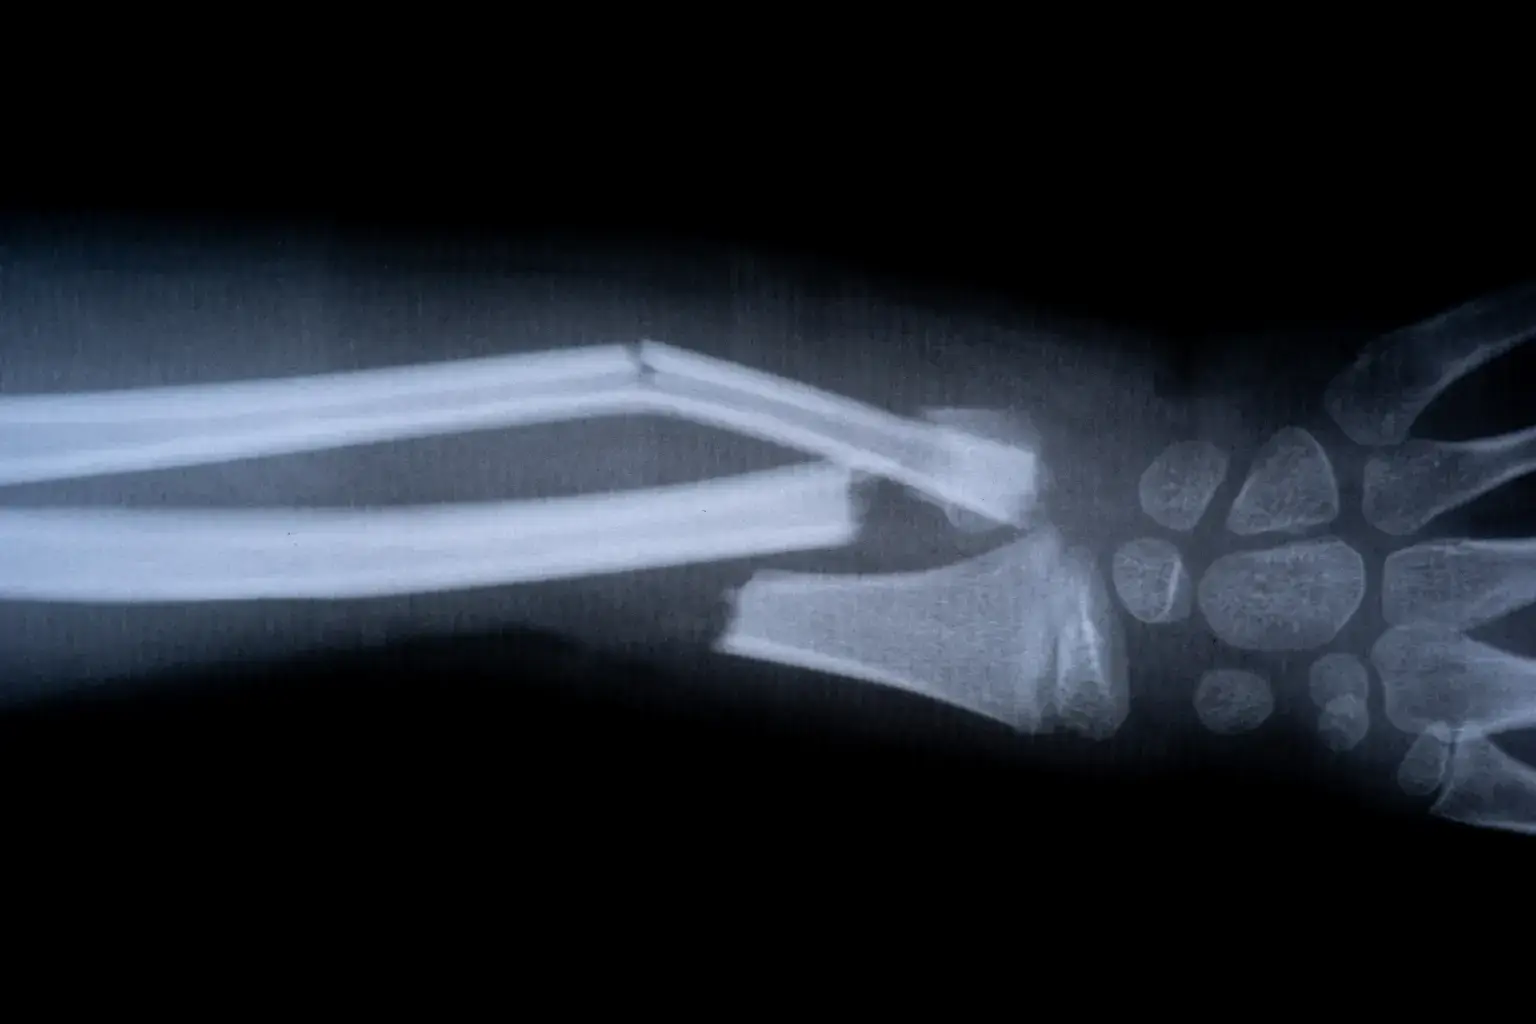

Liječenje se sprovodi jednom injekcijom, a ljepilo povezuje polomljene fragmente kosti u svega tri minute. U jednom od prvih slučajeva pacijent sa prijelomom ručnog zgloba primio je injekciju kroz rez od svega 3 cm i kost mu je zarasla za tri minute. Operacija bi, uobičajeno, zahtijevala ugradnju pločice i šarafa, te naknadnu intervenciju radi uklanjanja implantata. Na kontrolnom pregledu tri mjeseca kasnije, pacijent je bio potpuno izliječen, bez komplikacija.